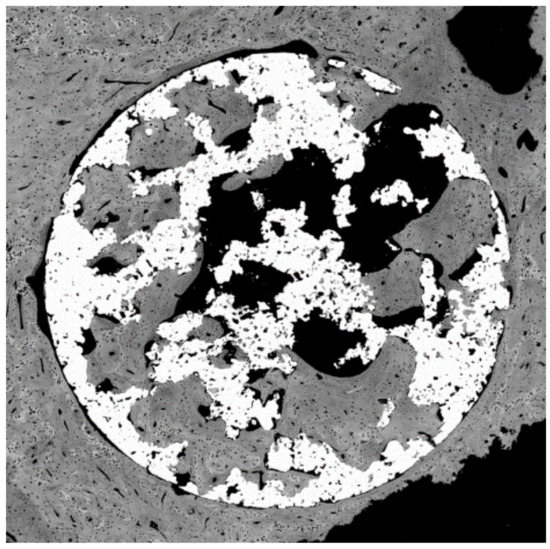

Since the spheres or porous materials obtained are composed of titanium, thermo-chemical treatments have been successfully carried out to obtain the sodium titanate layers that allow the formation of apatite in contact with the physiological medium, accelerating the mineralization process; therefore, the bone colonization will be faster. It was observed that the titanate layer obtained by the treatment is introduced in all the holes and channels of the implant; therefore, the material will have a high osteoconductive-specific surface for bone formation. This finding can be observed in Figure 16. Figure 17 shows a porous titanium material with thermo-chemical treatment in which the colonization and formation of new bone inside the pores of a dental implant can be observed.

Figure 16. Titanate gel and apatites on the porous titanium surface.